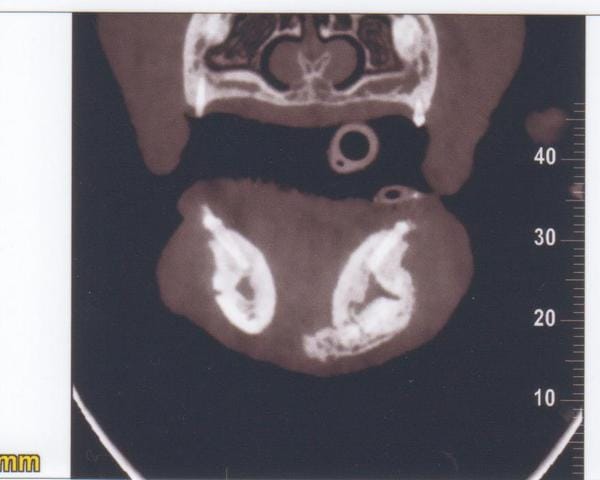

Cône Beam New Tom 5G

Technique : Examen des mâchoires en section axiale ; images natives de 0,1mm ; reconstruction MPR et 3D 0,1mm temps d’exposition total : 7.3s ; mAs : 23.08 ; kV 110kV ; CDTi/V (dose délivrée / surface exposée) : 3.27 mGy

Description

Mise en évidence d’une masse homogène se développant dans la base du menton avec néoformation osseuse de type proliférative.

Centre de la lésion au niveau de l’alvéole de la canine gauche absente et extension hauteur de PM3 pour la mandibule gauche et Pm2 pour la mandibule droite.

Limite carcinologique appréciée (5mm) en mésial des carnassières.